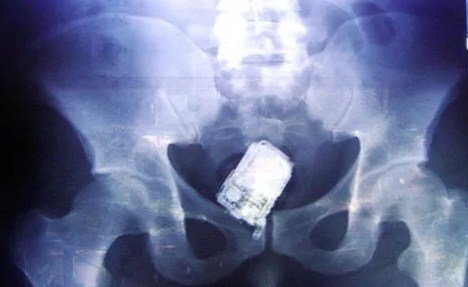

حقيقة نسيان هاتف خلوي ببطن مريضة

وكالة الناس – نفى وزير الصحة الدكتور سعد جابر صحة فيديو وخبر مفبرك يشير الى نسيان احد الاطباء هاتفه في بطن مريضة . وقال جابر ان الفيديو تم تداوله عام 2015 وتم نفيه أنذاك لعدم صحته، وقال ان وزارة الصحة نفت الحادثة عام 2015 واوضحت ان المريضة المقصودة كانت قد اجري لها عملية قيصرية بنيسان 2015، في احد المستشفيات العامة وبعد اسبوعين من العملية راجعت المستشفى نتيجة الام كانت تعاني منها.

واشارت الوزارة بتوضيحها انه بفحص وتصوير المريضة تبين ان الالام التي كانت تعاني منها ناتجة عن التهاب جرح العملية وقد تم ادخالها المستشفى على الفور والمباشرة في علاجها وخرجت من المستشفى بعد اتمام العلاج معافاة لا تعاني من اي مضاعفات.